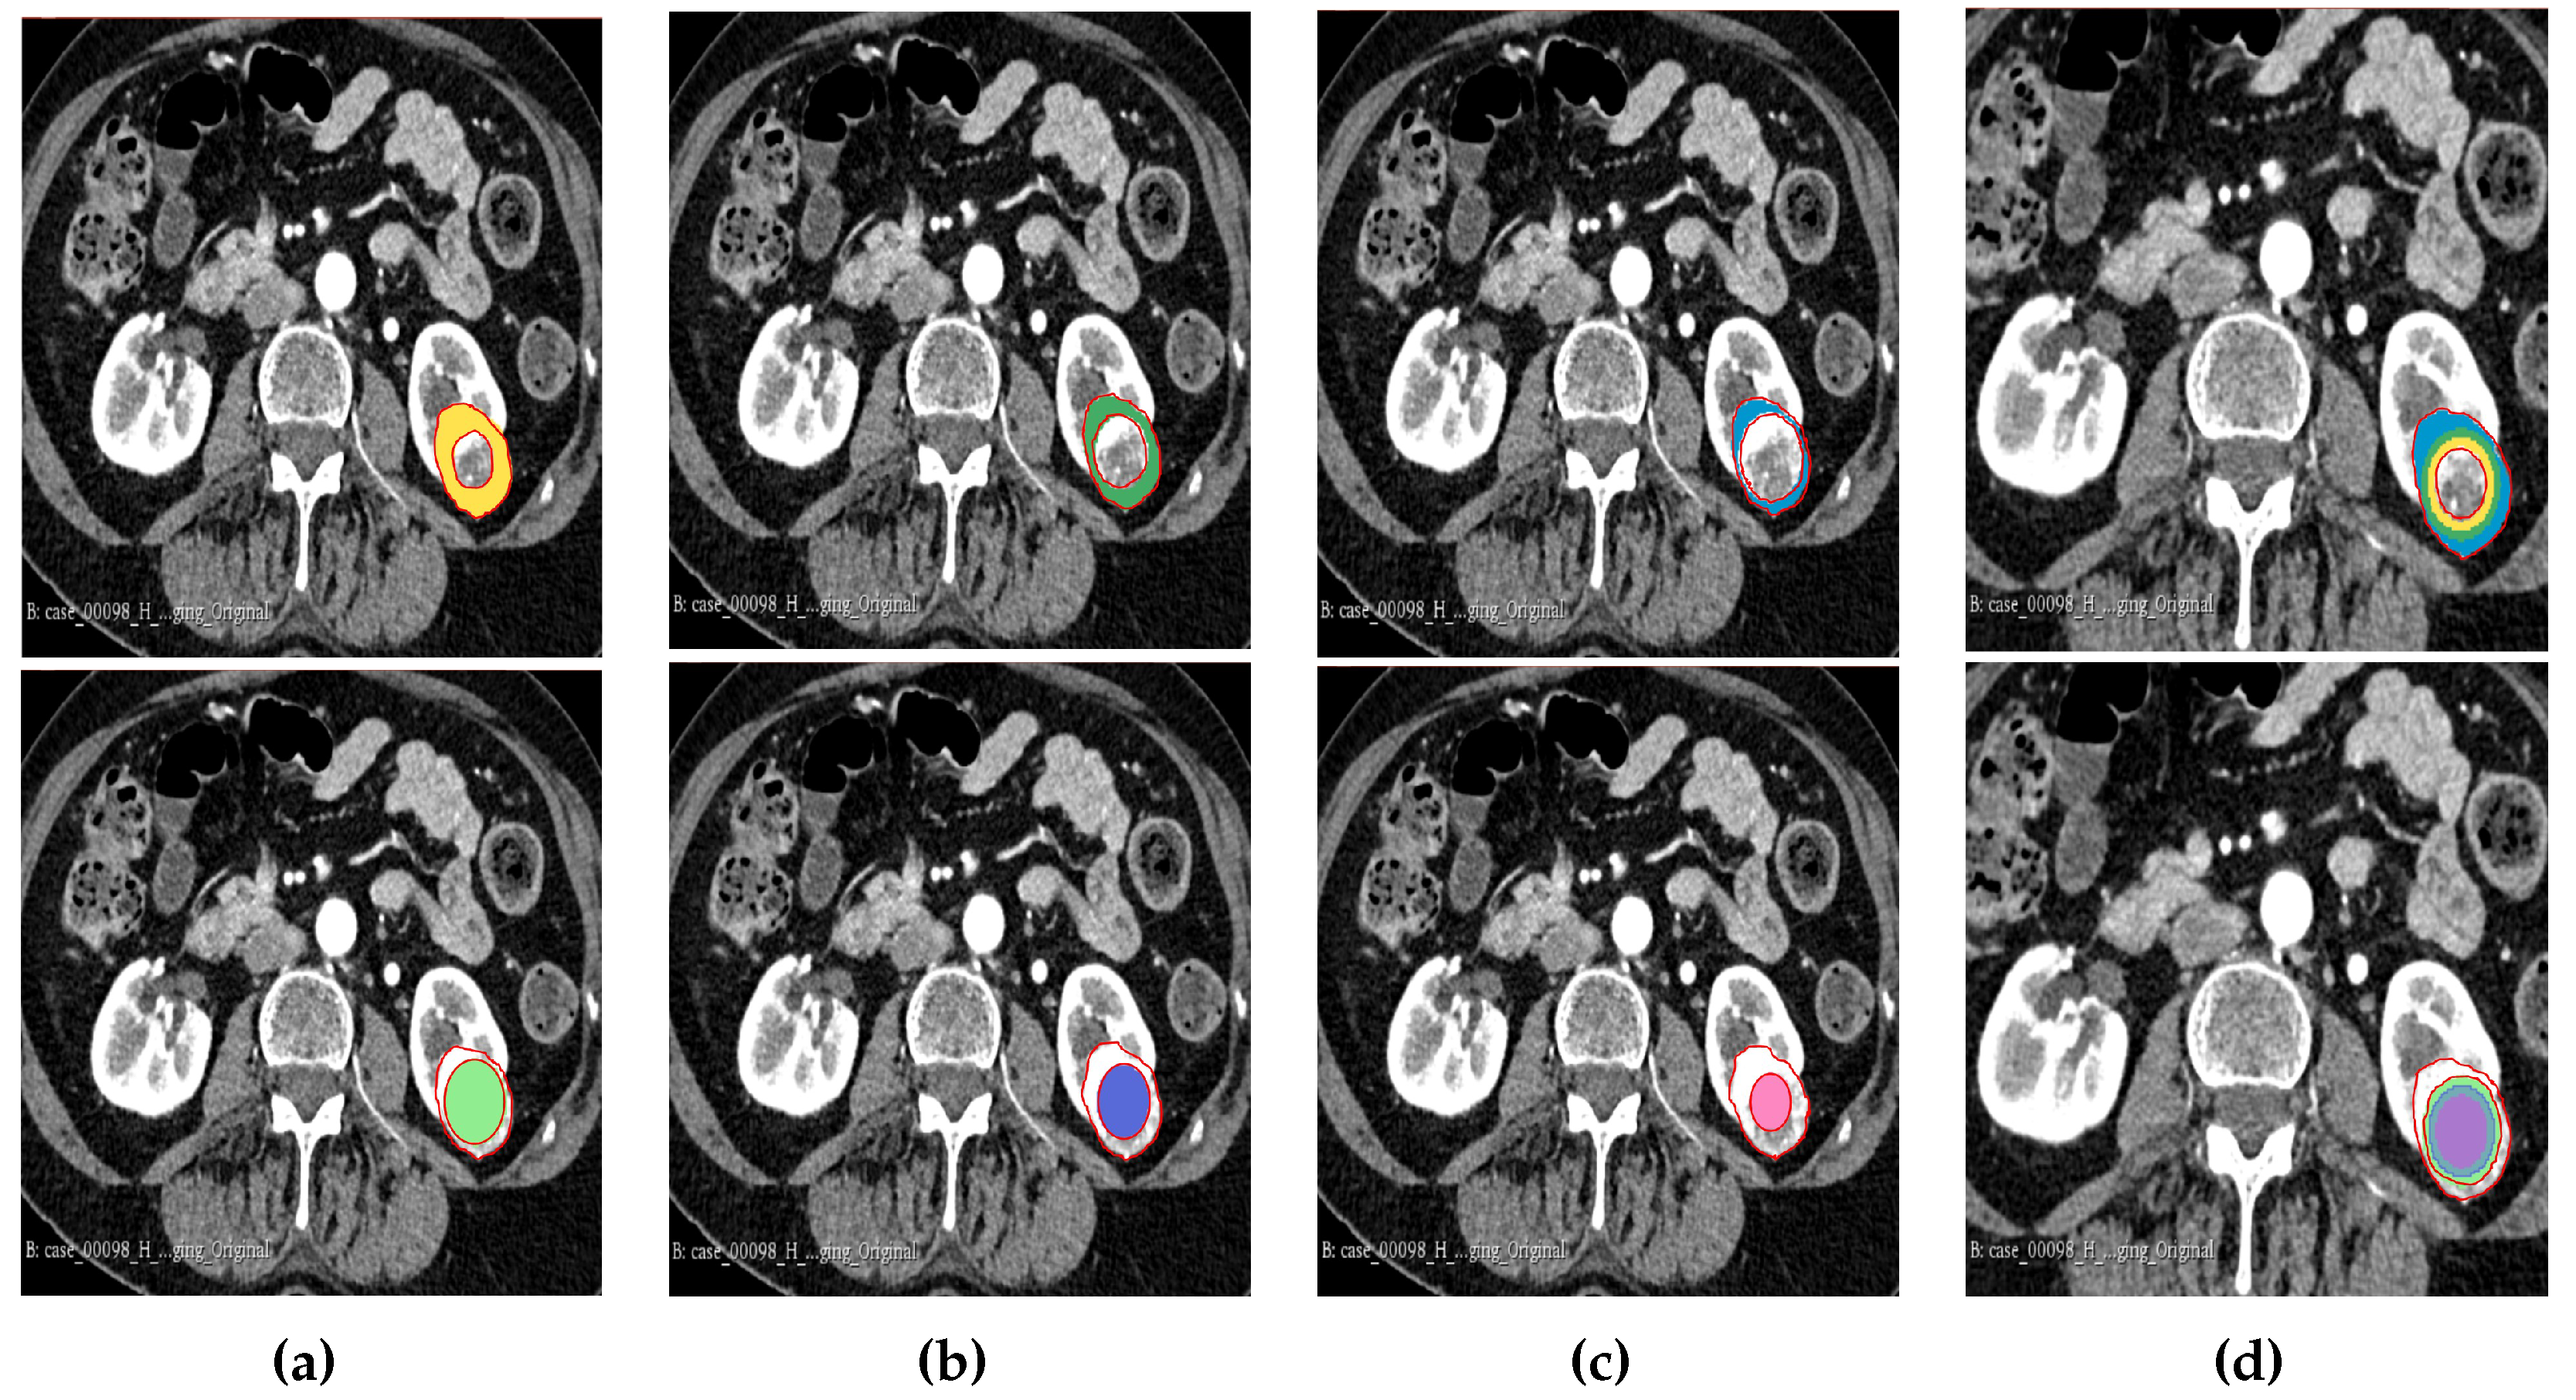

2.5. Tumour Sub-volume Segmentation Technique